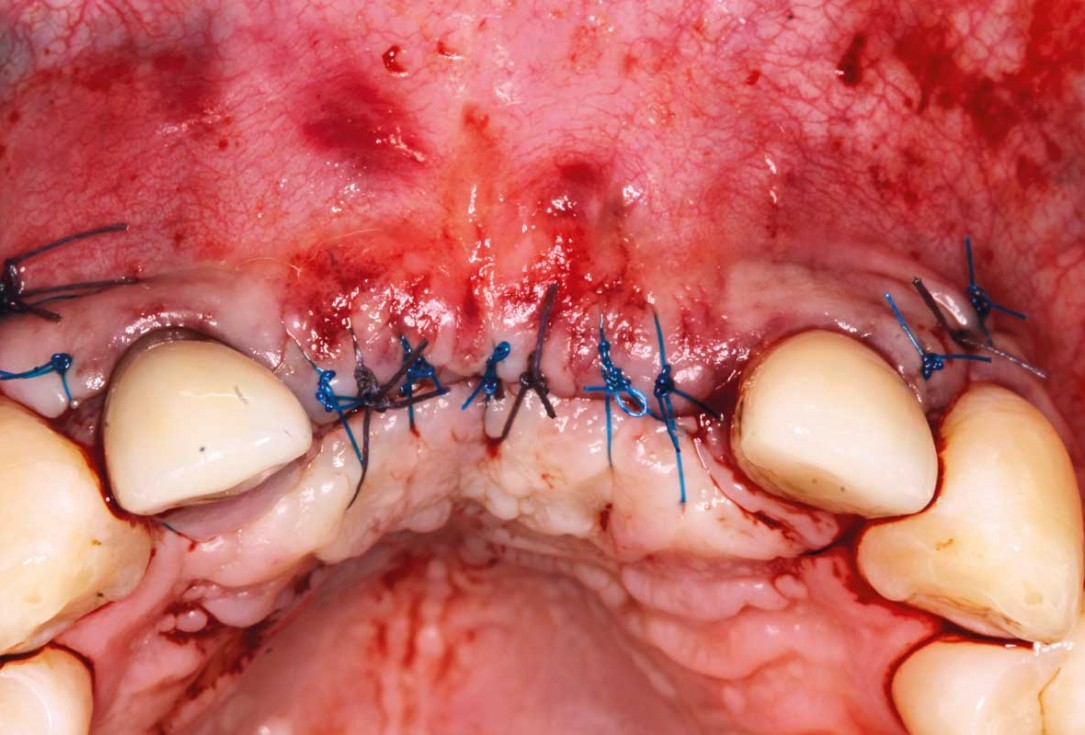

09/26 - Wound closure with 15 sutures

Ridge augmentation in the maxilla with maxgraft® bonebuilder in the aesthetic zone - Dr. M. Kristensen